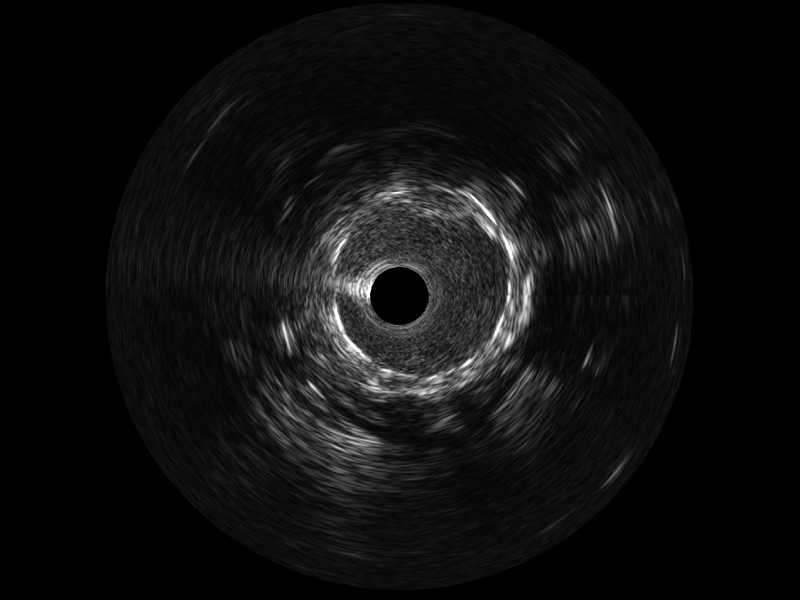

银河优越会宽频IVUS图像

对比传统IVUS导管成像,银河优越会宽频IVUS图像的近场支架梁显影更细腻,远场中膜外血管仍清晰可辨,兼顾远中近,兼顾分辨力与穿透深度